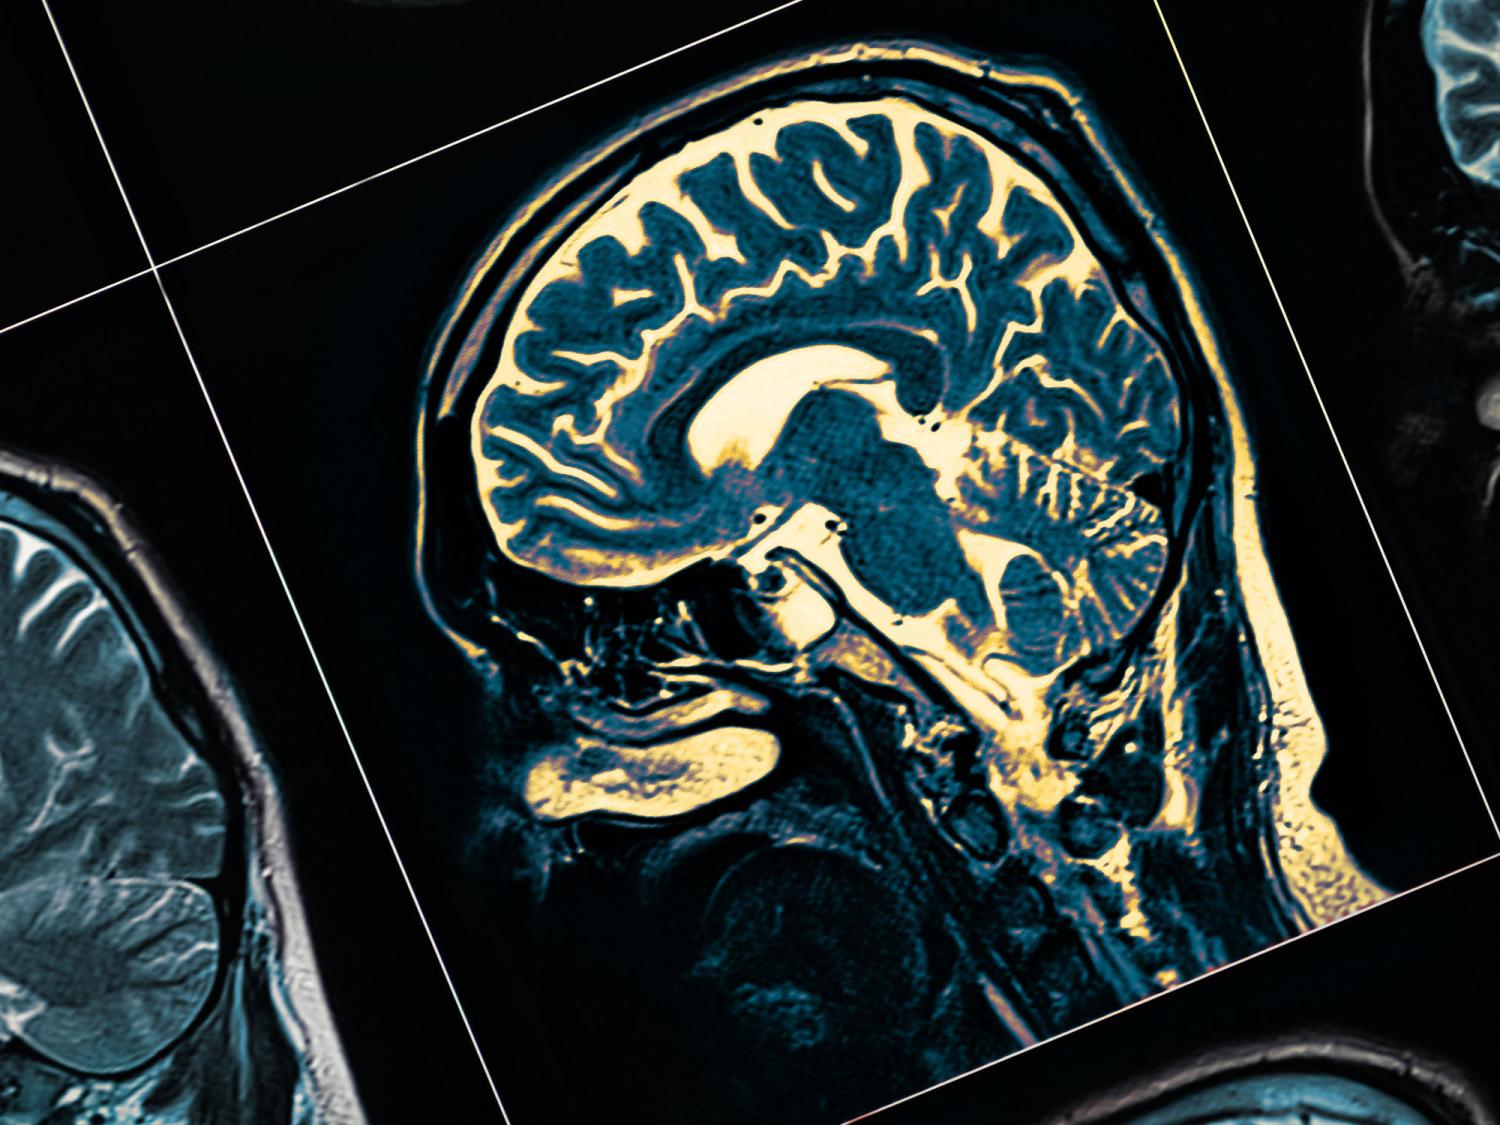

According to researchers at Penn State, artificial intelligence could offer a fast and effective way to screen for neurodegenerative diseases. Credit: sudok1/Getty Images. All Rights Reserved.